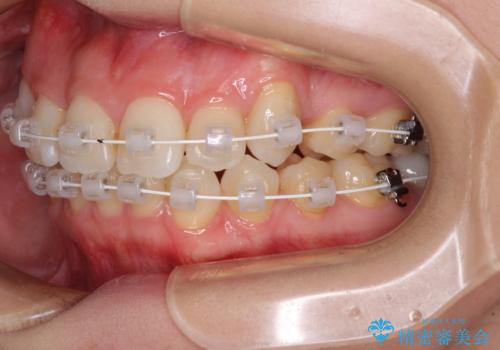

上顎の八重歯と下顎前歯の欠損 ワイヤー装置による抜歯矯正

- 上顎の八重歯を気にして来院された患者様です。

診察したところ、下顎前歯が2本欠損していたため、上下のバランスを取りながら八重歯を改善するため、上顎左右第一小臼歯2本を抜歯することとしました。

下顎左右大臼歯の歯根部に病変があったため、矯正治療前に根管治療を行い、矯正治療後にセラミッククラウンによる補綴治療を行うこととしました。

下顎前歯と本来抜歯矯正で抜歯する歯とは大きさが異なるため、仕上がりの咬み合わせは理想的なものとはなりませんでしたが、気になっていた八重歯はきれいに改善することができました。